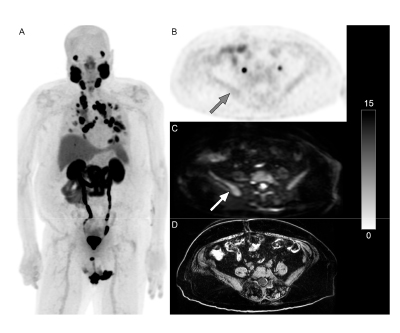

Whole-Body Diffusion-Weighted Imaging Spots PSMA-negative Lesions

PET/MRI with metastases, minimal PSMA activity in pelvic bones, but osseous metastases,  and a T1-weighted image. Figure 2.

Adding whole-body diffusion-weighted imaging (WB DWI) to PSMA PET scans for patients with metastatic castration-resistant prostate cancer can allow radiologists to identify PSMA-negative lesions, potentially altering their treatment plan. The most common locations for these lesions were the lymph nodes followed by bones and, less frequently, the lungs and liver.

This research was published in the Journal of Clinical Medicine in March 2025.

Authors: Cheng William Hong, Spencer Behr, Fei Jiang, Yingbing Wang, Sina Houshmand, Thomas Hope